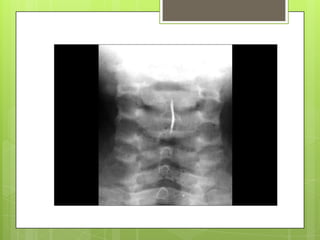

DIAGNOSIS

 Roentgenographic

examination.

or fluoroscopic